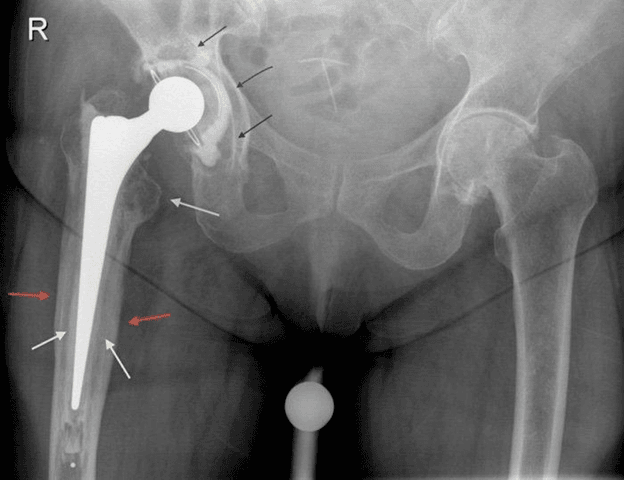

The patient, who had previously undergone a hip replacement in 1997, went to the orthopedist after suffering from hip and buttocks pain for several months.

Fortunately for her, after several months of intense pain, she was injected with many antibiotics to kill the infection, and got a new artificial hip. By her last examination 15 months after surgery, doctors reported that she worked well with a pain-free hip, although the mysterious and painful memory of the bacteria (Capnocytophaga canimorsus) could not easily be forgotten.